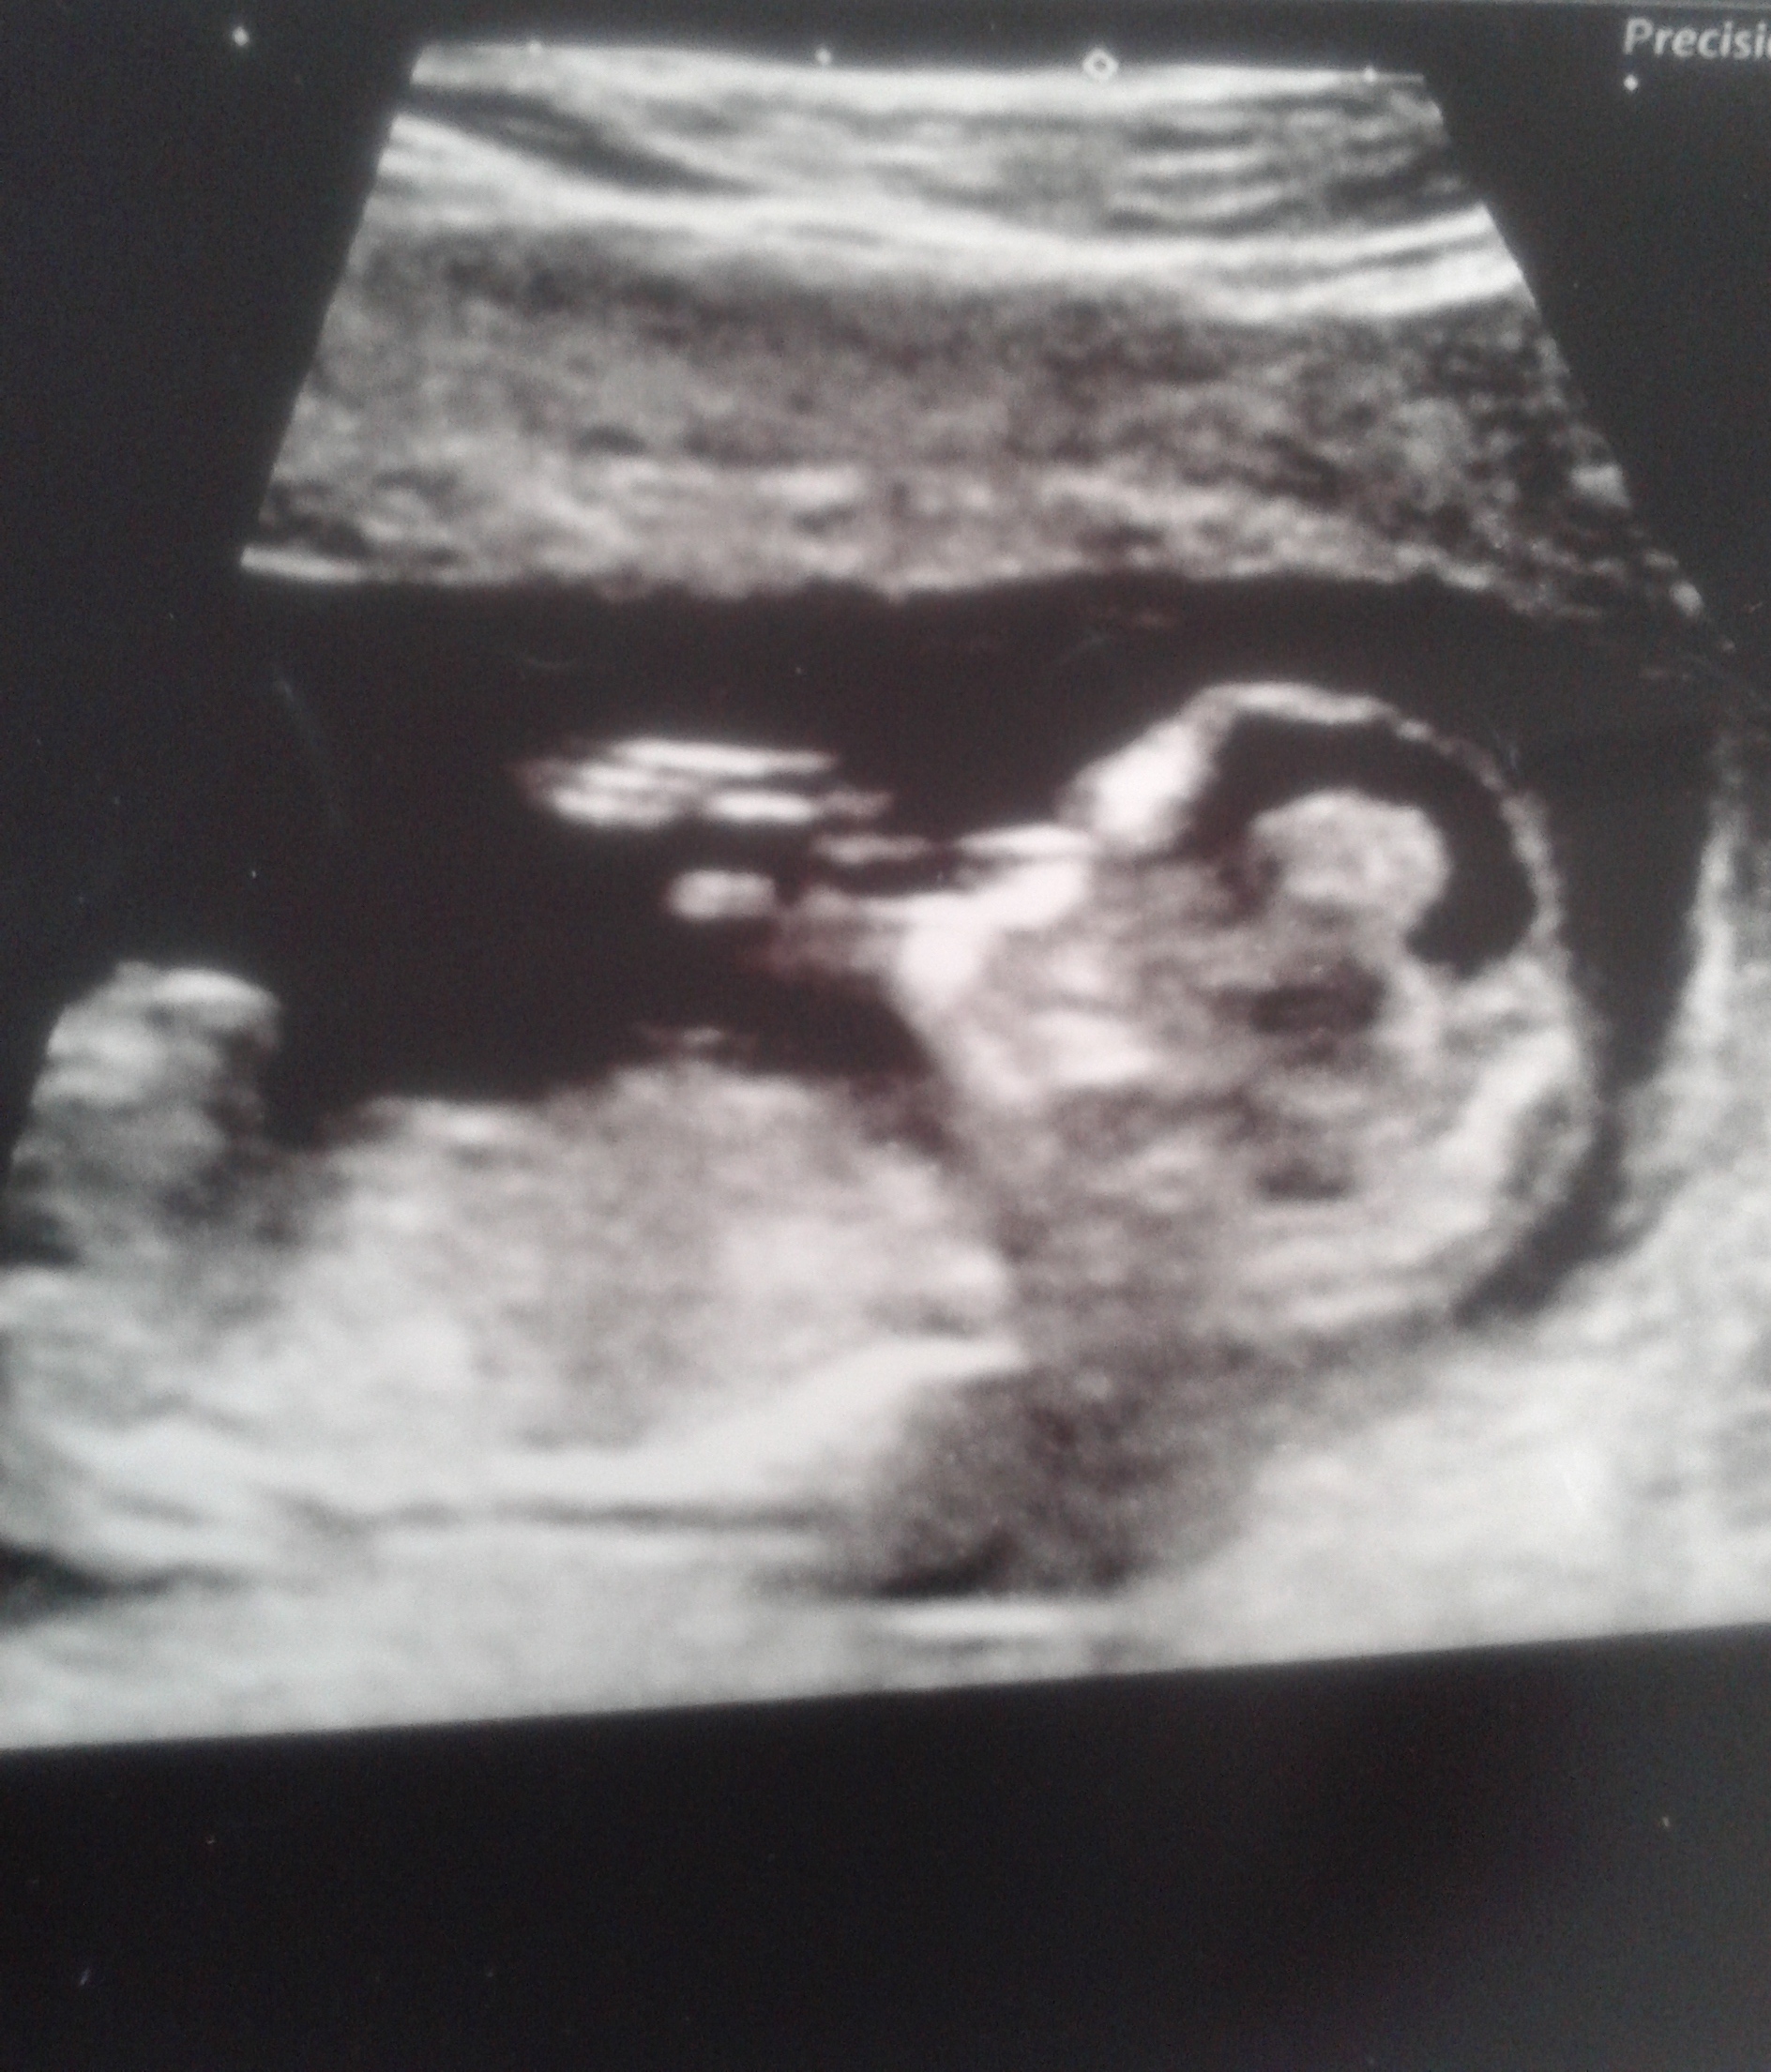

take a guess please.Attachment 19154 https://imageshack.com/a/AnNq/1 thanks

I don't think the nub is totally captured if at all but if what I see is the nub then I would lean boy!

hi theres no nub. just skull theory.